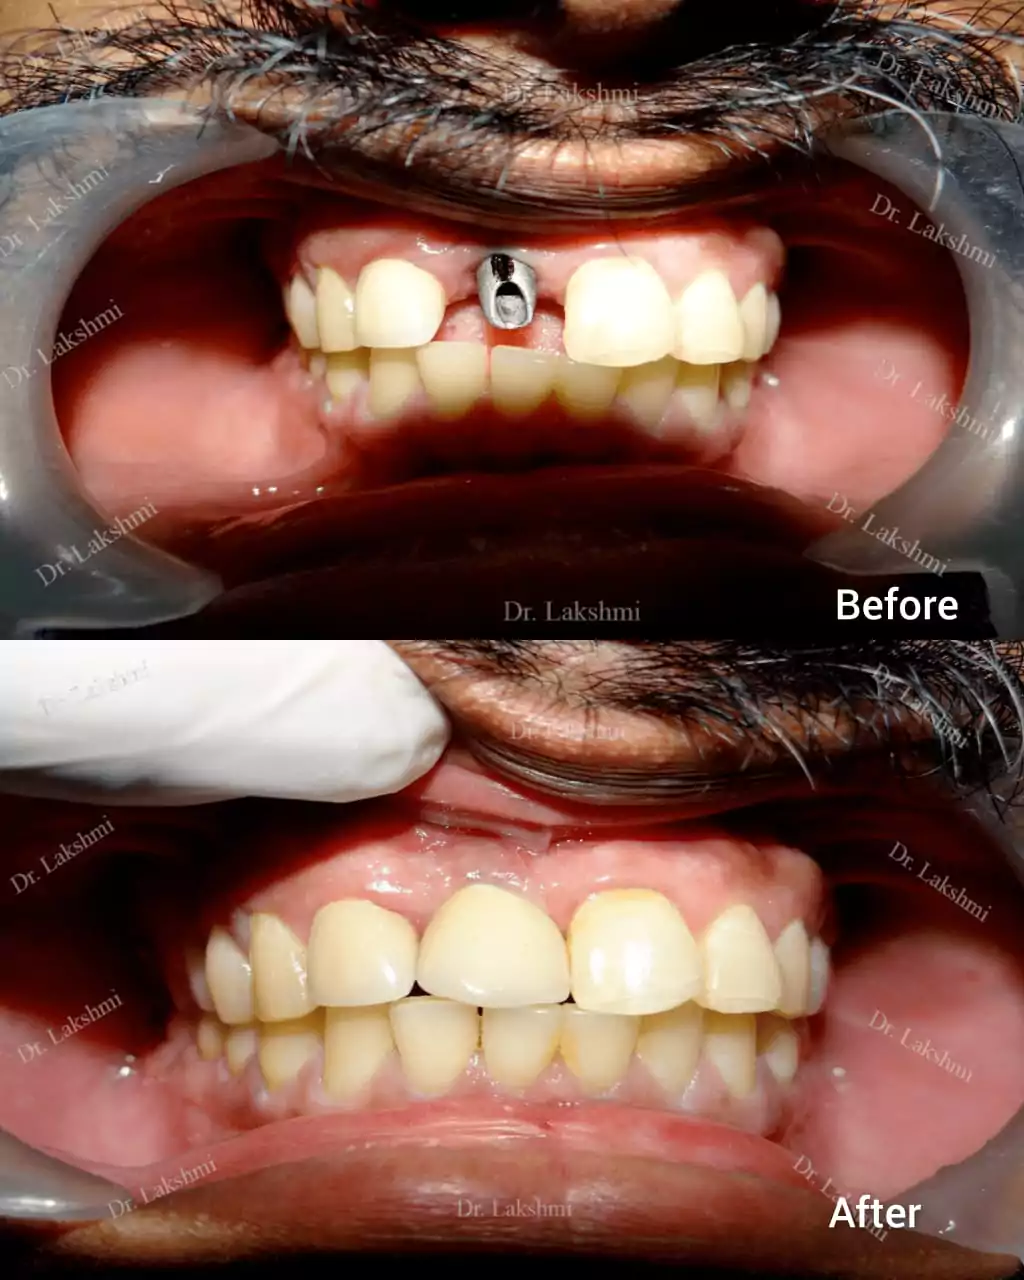

Dental implants have come to define modern dentistry in the last few decades. Dental implants are cemented to the jawbone and an abutment is used as a support for the dental crown that is placed over it. There are a single piece, two-piece and three-piece abutments available for implants. Titanium fuses naturally with the jawbone and that makes it a perfect fit as an implant. There are several dental implant techniques available to opt from, for a patient. The freedom to opt also depends on the condition of the jawbone and the gum.

Requires the placement of a single dental implant (either 2 stage or 1 stage) in the region of the missing tooth, followed by a crown (artificial tooth) over

Treatment Duration: 2 stage dental implants: The replacement is completed in 2 stages which are spread over an interval of minimum 3 months. The first stage involves the placement of the implant and requires one to two sittings,Temporary Crowns will be given to the patient. The second stage involves the placement of the artificial tooth (Permanent crown).

1 stage dental implant: Requires just one stage for the placement of the implant and crown(Permanent Crown).